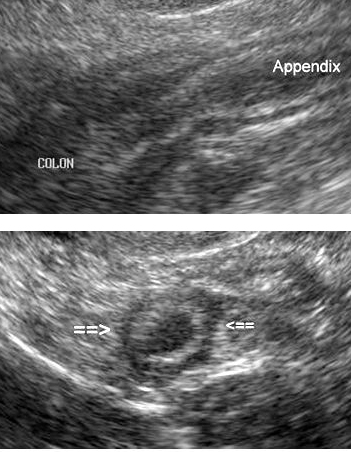

- Echographie

du tube digestif peu recherche d'une

epaissisement de la paroie du tractus digestif , une

masse intraparietal , lesions inflamatoires (

appendicite ) |

| Images echographiques de

appendice inflame en coupe transverse ( signe Halo)

et coupe longitudinal incline .** |

Appendicite aigue

en coupe tranverse et longitudinal . Echographies

|

Image echographique de

iinvagination ileo-coecal . Image en cocarde |